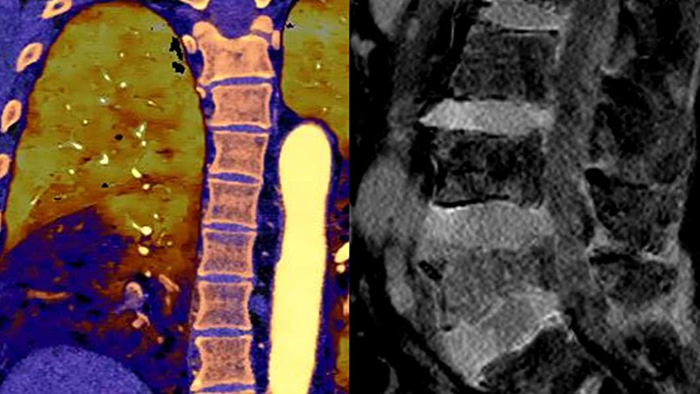

Go beyond conventional CT. See how layers of spectral-detector results can enhance your diagnostic confidence.

Neck mass